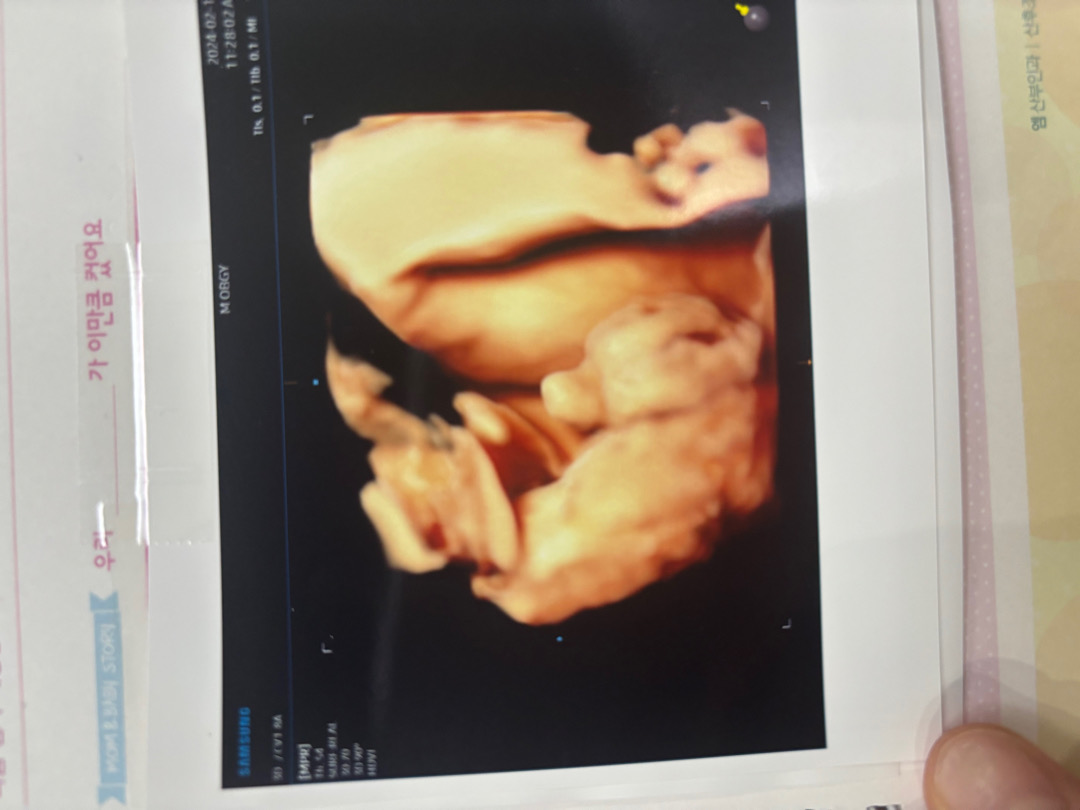

얼굴도 안보여주고 고추만 잘보여준다며 선생님이 고추사진을 입체초음파로 찍어주셨네요…? 푸짐하죠..? 33주 1일 배는 만삭수준인데 애기는 또 배나온거에 비해 많이 안커서 2.2키로 라며 제왕으로 출산예정인데 이대로라면 3.2에 나올 수 있겠다시네여 .. 아직 애기가 안커서 수술날짜는 아직이라며 안잡아주셔요 ㅜㅜㅜㅜ 수술하게되면 3월 25~27일쯤 될거같긴 하다고 하시는데 … 남편 생일이 3월 31일인지라 .. 안겹쳤음 좋겠네여 ㅋㅋㅋㅋ